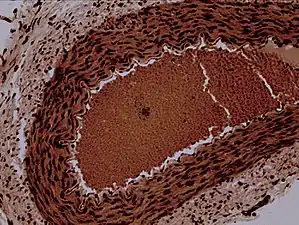

![]() Rabbit arteriole at 100X | |

Arterioles have muscular walls (usually only one to two layers of smooth muscle cells) and are the primary site of vascular resistance. The greatest change in blood pressure and velocity of blood flow occurs at the transition of arterioles to capillaries. This function is extremely important because it prevents the thin, one-layer capillaries from exploding upon pressure. The arterioles achieve this decrease in pressure, as they are the site with the highest resistance (a large contributor to total peripheral resistance) which translates to a large decrease in the pressure. [2]

Microanatomy

In a healthy vascular system the endothelium lines all blood-contacting surfaces, including arteries, arterioles, veins, venules, capillaries, and heart chambers. This healthy condition is promoted by the ample production of nitric oxide by the endothelium, which requires a biochemical reaction regulated by a complex balance of polyphenols, various nitric oxide synthase enzymes and L-arginine. In addition there is direct electrical and chemical communication via gap junctions between the endothelial cells and the vascular smooth muscle.